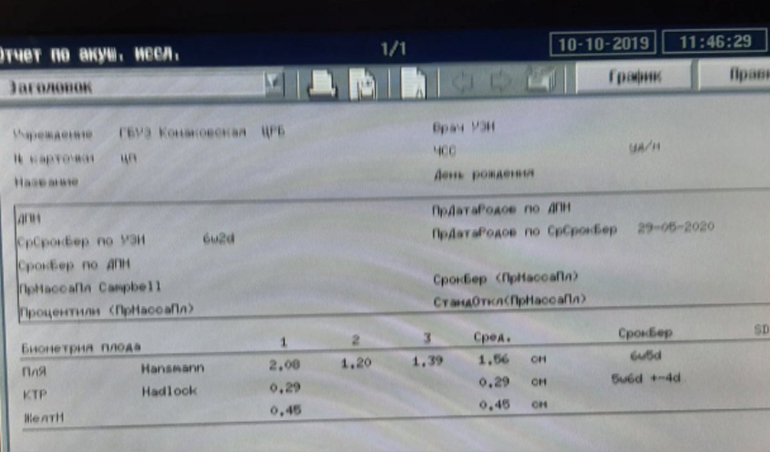

УЗИ ПЕРВОЕ)) 6 НЕДЕЛЬ)

МАЛЫШ 2 ММ ВСЕГО))) СЕРДЕЧКО ПОКА НЕ ПРОГЛЯДЫВАЕТСЯ) НО ВЫРОС ХОРОШО)

МАЛЫШ 2 ММ ВСЕГО))) СЕРДЕЧКО ПОКА НЕ ПРОГЛЯДЫВАЕТСЯ) НО ВЫРОС ХОРОШО)